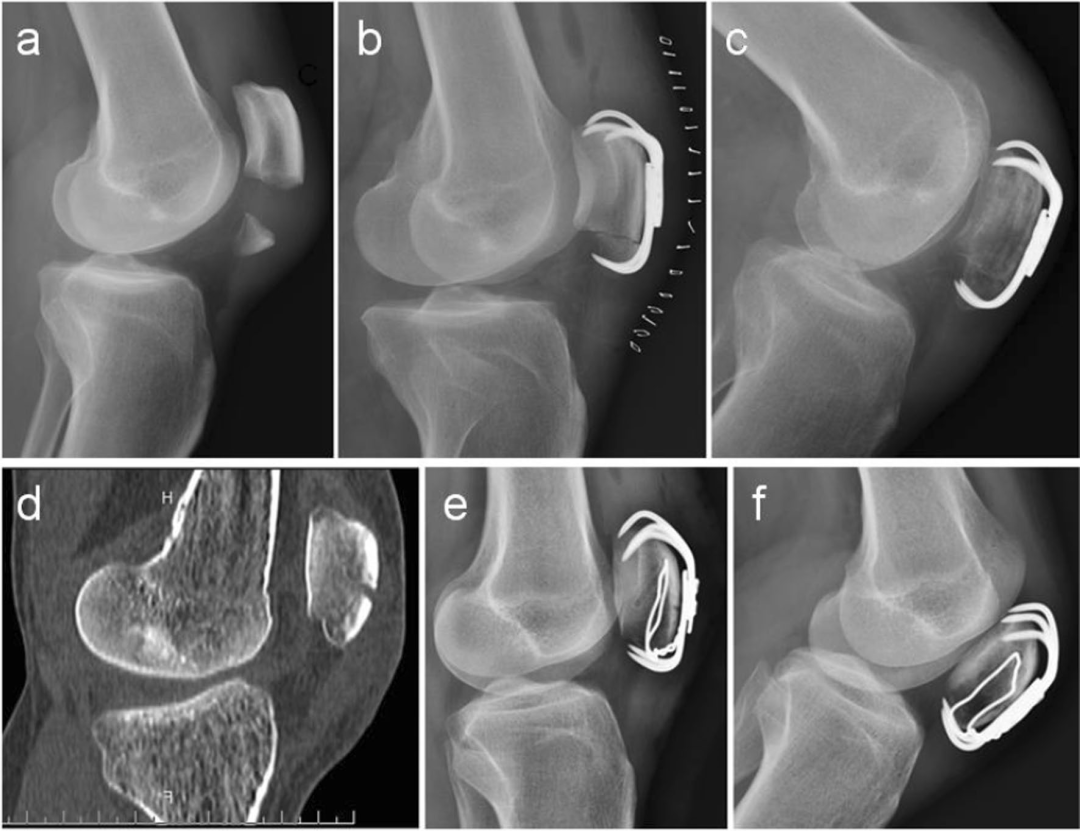

扎骨针怎么装髌骨下极粉碎骨折怎么办?7种固定技术详解与术式选择_https://www.jmylbn.com_新闻资讯_第8张

图2. 最短的3.5 mm钩钢板(Synthes GmbH,瑞士)经过裁剪和预成形,以适应髌骨的长度和形状(A-F)。

术中透视确认解剖复位后,通过硬膜外套管引导1.0 mm钛索(Synthes GmbH, Switzerland)环扎术环绕整个髌骨。将3.5 mm的钩钢板(Synthes GmbH,瑞士)修整并预塑形,以适应髌骨的长度和轮廓(图2)。然后用钩的尖端穿透钢缆环扎的远端及其下方的髌腱,以防止髌腱纤维撕裂。然后,使用滑动加压技术将3.5 mm的皮质螺钉偏心地固定于钢板的最近端孔。

根据需要,将4.0 mm空心半螺纹螺钉由远端向近端置入,并结合垫圈通过钢板两个钩之间的远端孔置入。这是由于钩钢板远端孔的直径接近于从远端向近端置入的空心螺钉的外径。因此,没有垫圈螺钉将通过远端孔

此外,垫圈可以防止螺钉头成为应力提升器,穿透粉碎的髌骨下极,并让压缩力通过垫圈和钢板的两个挂钩传递。值得注意的是,这一步骤是由x线透视引导的,这对于确认可用的轨迹是必要的。修复支持带撕裂。通过目测和透视检查进行全范围被动运动。伤口用可吸收缝线(#2 Vicryl®)分层缝合。患者离开手术室前常规获得患膝的标准正侧位片。(图3和4)。

图3. 病例(例4,55岁,男性,右侧)。术前正位(A)和侧位(B) x线片显示髌骨下极移位骨折。术后正位(C)和侧位(D) x线片。2年随访时的x线片(E-F)和功能(G-I)。